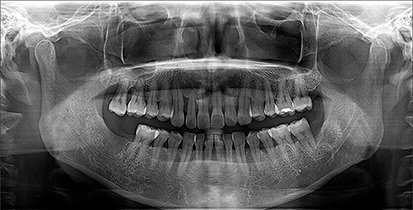

Orthopantomogram (OPG) is a panoramic dental X-ray that captures the entire mouth in a single image, including teeth, jaws, and surrounding structures. It is commonly used to diagnose dental issues, plan treatments, and assess jaw health.